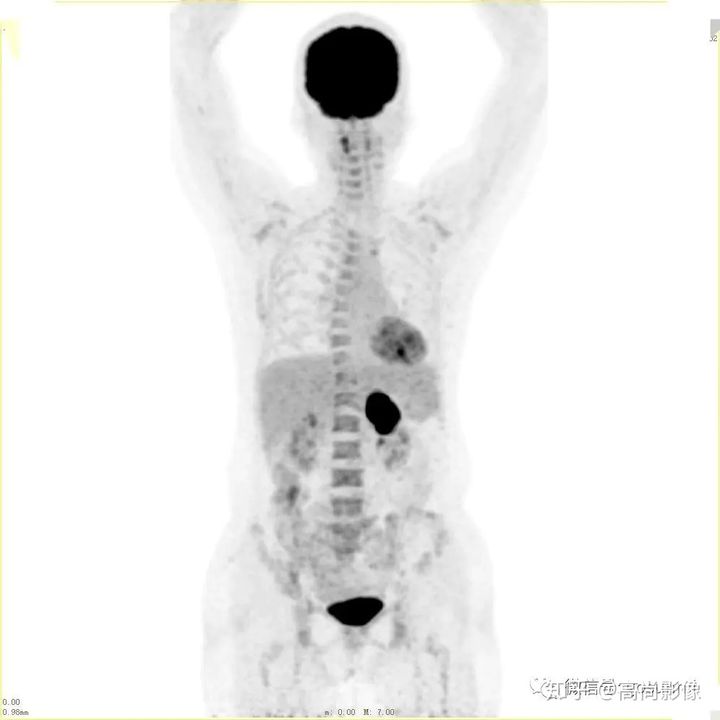

(右肺癌全身多發(fā)轉(zhuǎn)移)

肺癌化療前評估的MIP圖

(最大密度投影圖)

肺癌化療后評估的MIP圖

由此可見,惡性腫瘤化療前后的全身PET/CT評估有多重要,尤其對于惡性腫瘤患者來說,時間就是生命,早一天完善診斷,早一天得到正確的治療,預(yù)后就會更佳。